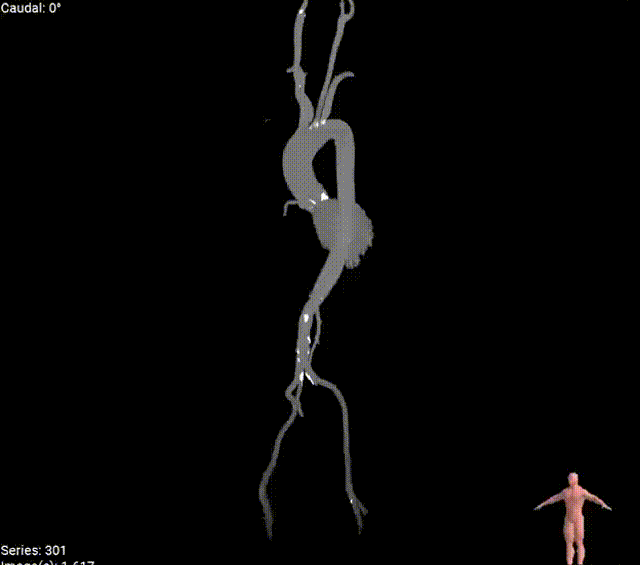

根部动图

外周动图

外周入路

外周入路尚可